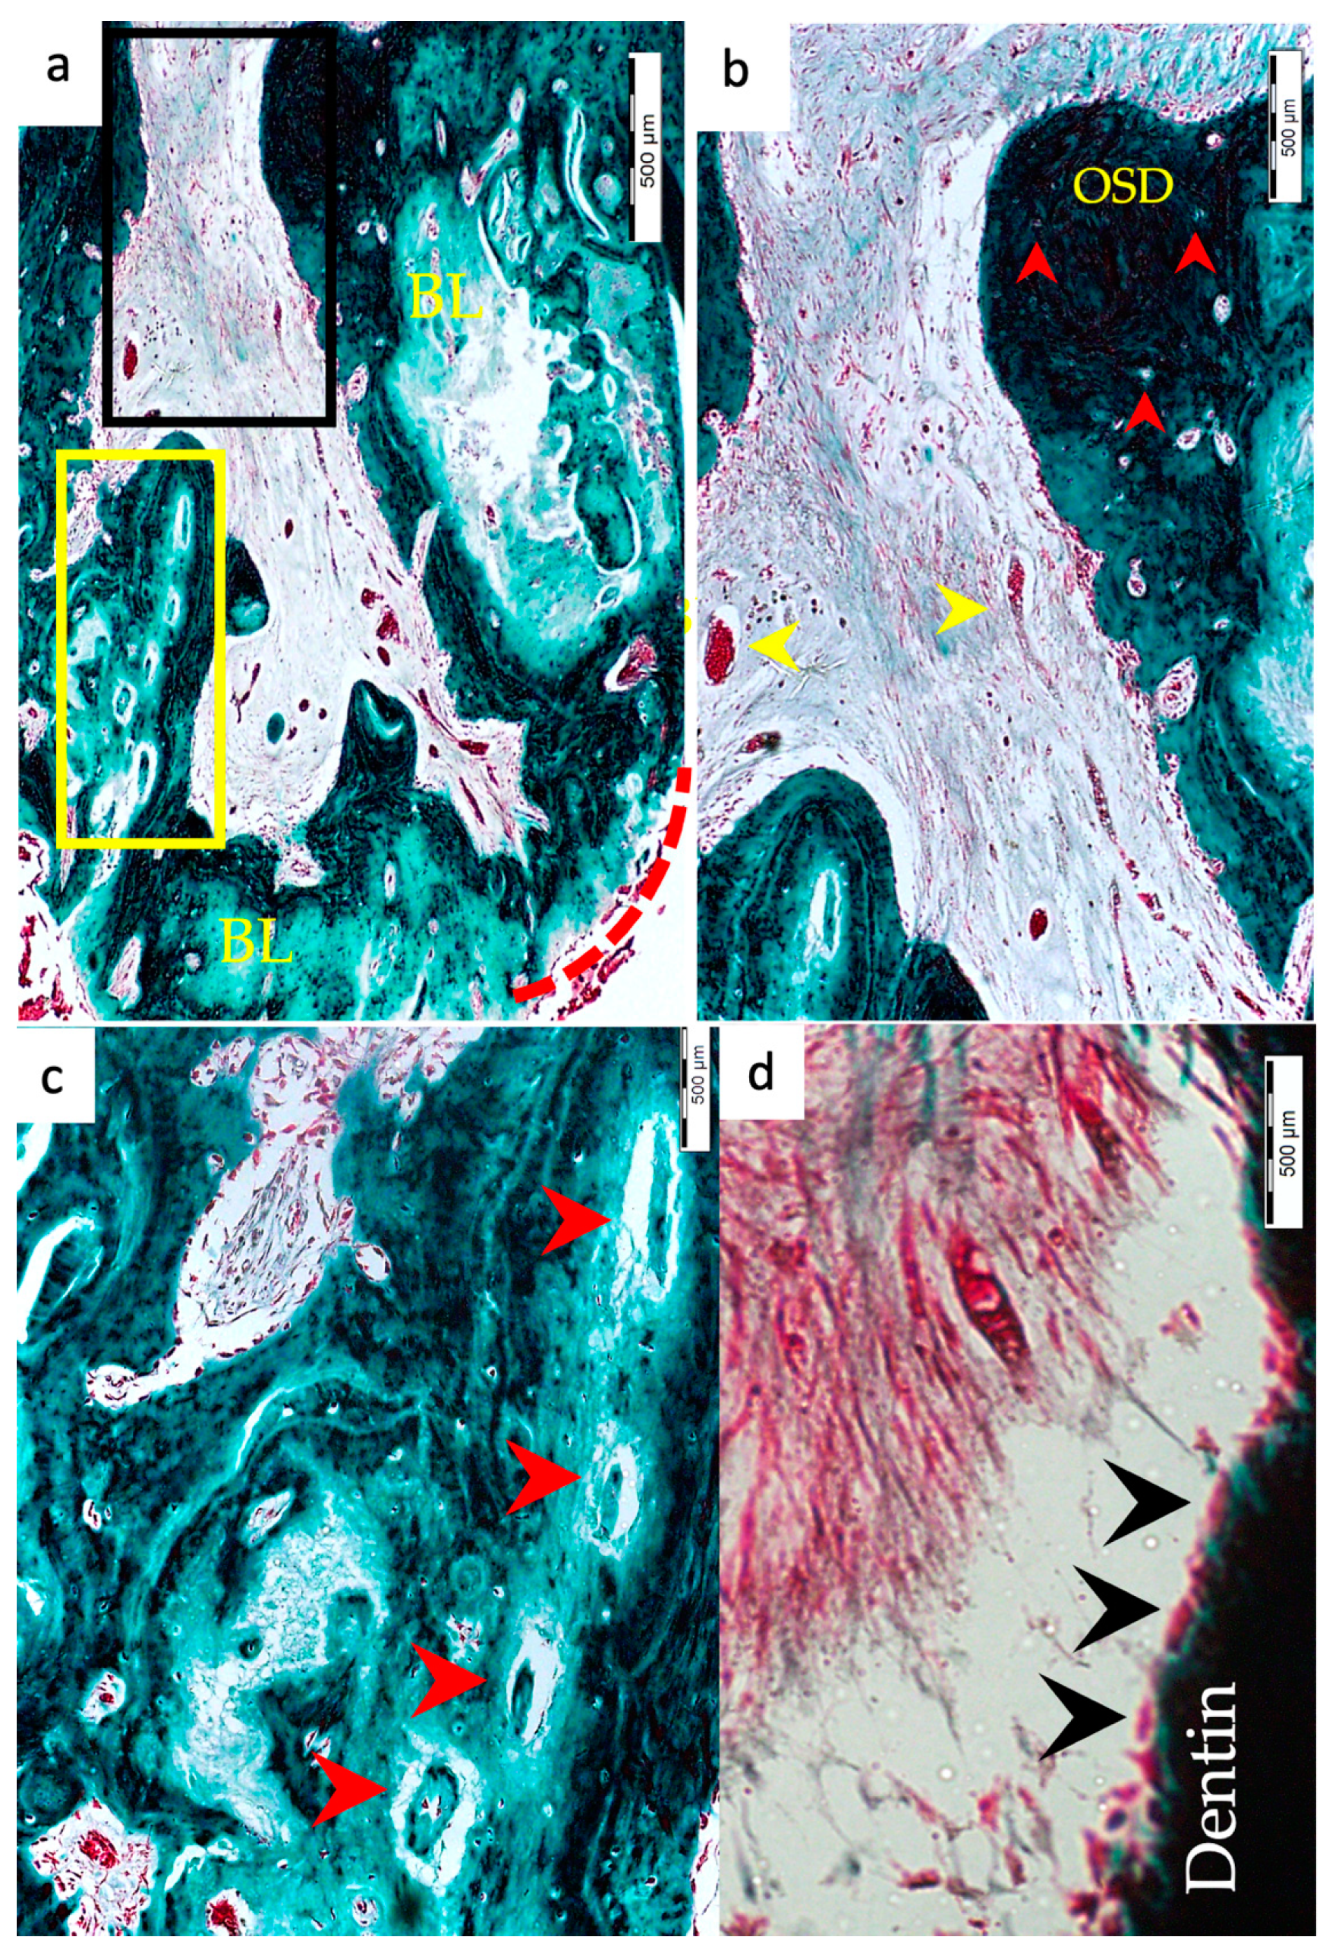

3.1. Hard Tissue Deposition

3.2. Type of Hard Tissue Formed

3.3. Vascularization and Formation of Vascularized Soft Connective Tissue

3.4. Degree of Inflammation

3.5. Apical Closure